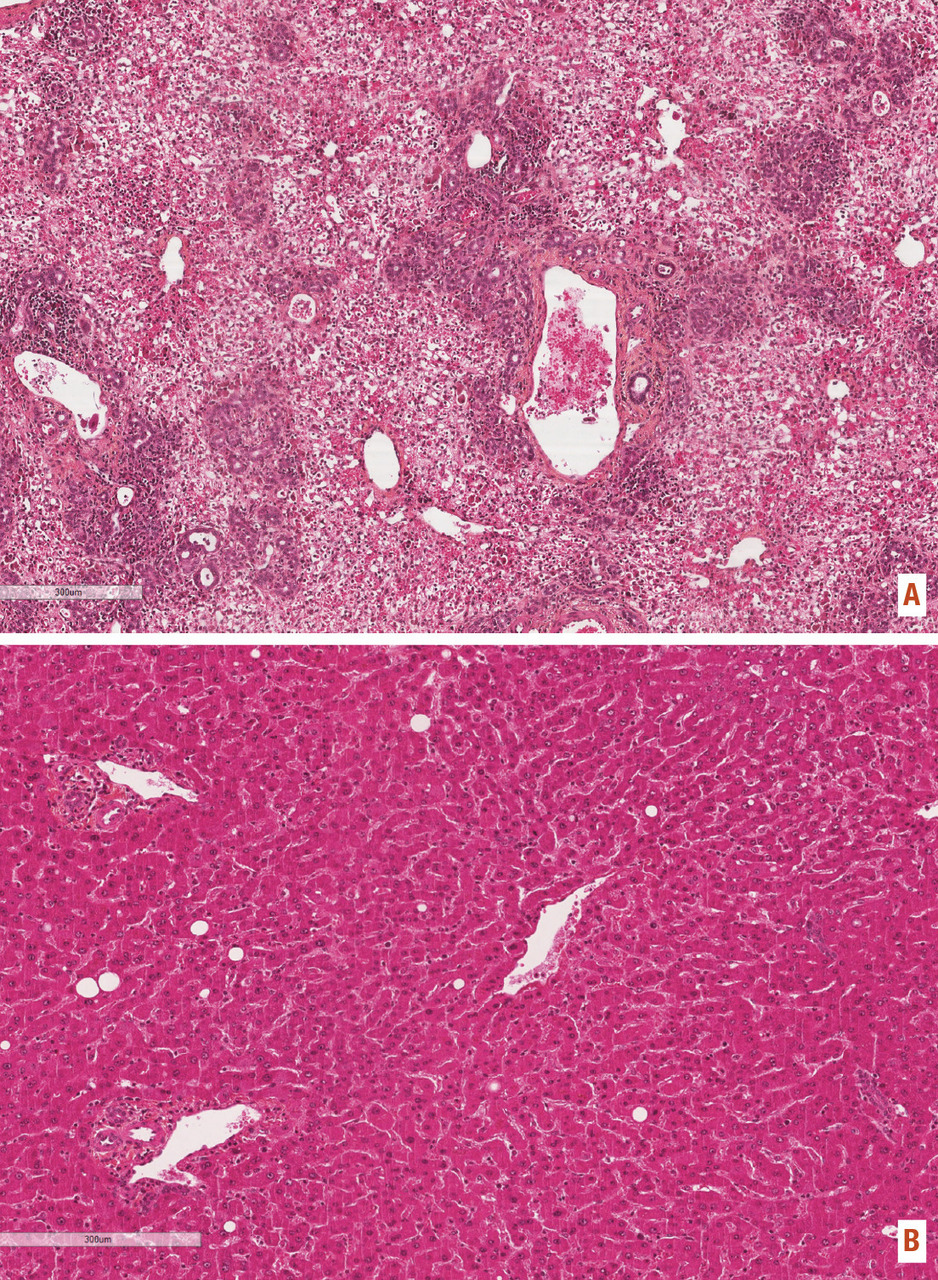

Ponction-biopsie hépatique

Lorsque les données cliniques, biologiques et d’imagerie ne permettent pas de faire un diagnostic étiologique, la ponction-­biopsie hépatique est nécessaire. Elle peut apporter un faisceau d’arguments qui, même s’ils ne sont pas spécifiques, orientent vers une cause donnée. Elle permet également de déterminer le stade évolutif (extension de la nécrose hépatocytaire pour les maladies aiguës, extension de la fibrose pour les maladies chroniques). Si l’hépatomégalie est diffuse, la biopsie est en principe réalisée dans le lobe droit, et un contrôle échographique est recommandé (fig. 8) ; à l’inverse, lorsque qu’il existe un ou plusieurs nodules, elle doit être faite en foie nodulaire et en foie non nodulaire pour rechercher une hépatopathie sous-jacente.

Les contre-indications à la ponction-biopsie transpariétale sont l’ascite, les troubles de l’hémostase non corrigés (taux de prothrombine inférieur à 50 %, plaquettes inférieures à 60 G/L, temps de céphaline activée [TCA] ratio supérieur à 1,5) et une dilatation des voies biliaires. Les deux premières contre-indications peuvent être contournées en effectuant la biopsie par voie transjugulaire.